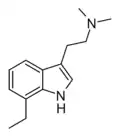

| Chemical structure | Short Name | Origin | Ring Substitution | RN1 | RN2 | Full Name | CAS Number |

|---|---|---|---|---|---|---|---|

| 7-Ethyl-DMT | artificial | 7-CH2CH3 | CH3 | CH3 | 7-ethyl-N,N-dimethyltryptamine | |